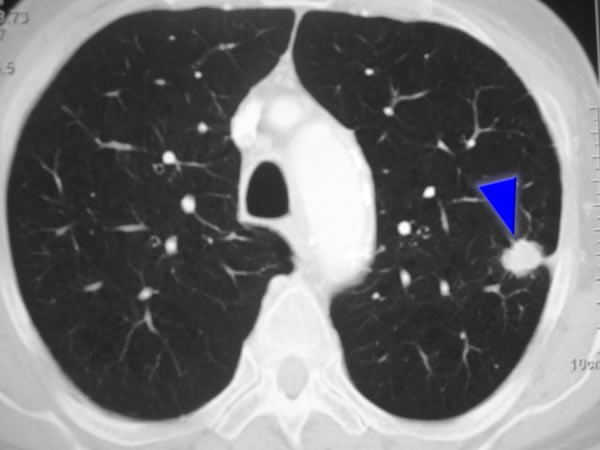

Suplementación con vitamina D para prevenir infecciones respiratorias agudas: revisión sistemática y metanálisis de datos agregados estratificados

25 febrero 2025

Este metanálisis actualizado arrojó una estimación puntual similar al obtenido anteriormente para el efecto general de la suplementación con vitamina D sobre el riesgo de infecciones respiratorias agudas, pero el IC del 95% para esta estimación del efecto ahora incluye 1,00, lo que indica que no hay protección estadísticamente significativa. The Lancet Diabetes & Endocrinology, 21 de febrero de 2025